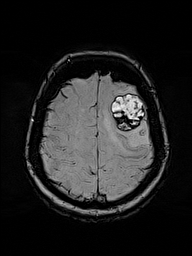

MRI Brain w/ Contrast

Baseline → Follow-up (Δ 14 days)

eigenMRI Filtered

MRI view

Local Lesion Window · Lesion Origin (Tracked)

Local lesion window

Lesion Origin anchor for longitudinal tracking

ABER anatomic boundary emphasis region

Overlay margin / curvature / global

eigenMRI is a deterministic reconstruction framework that applies eigenmode and Laplacian-based spectral analysis to standard MRI data. It enhances structural continuity, boundary definition, and subtle tissue transitions without modifying scanner hardware, pulse sequences, or contrast agents.